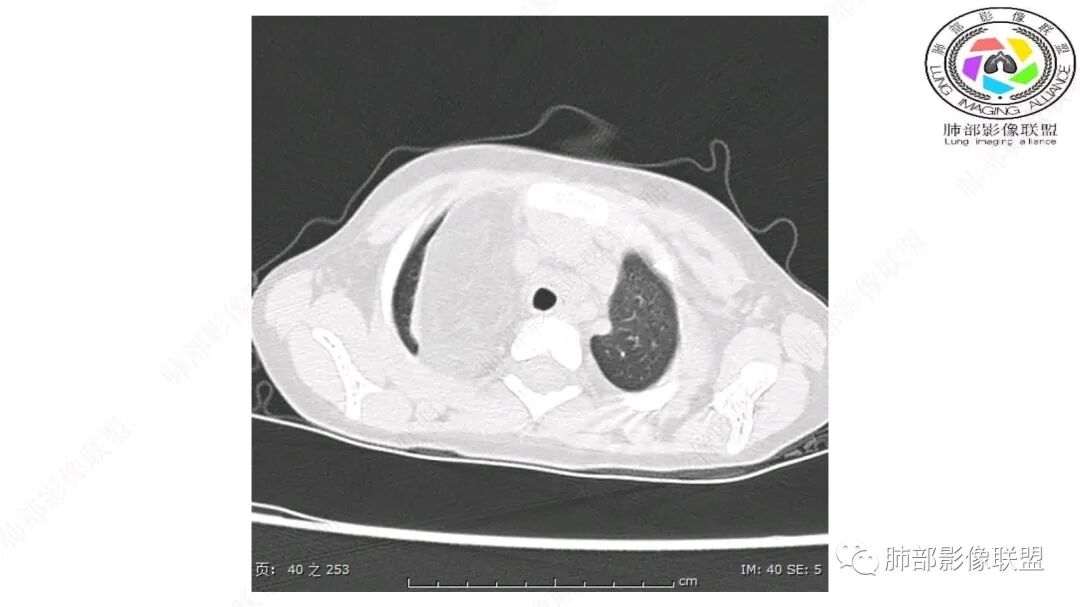

病灶属于交界区,主体位于肺内,占位效应明显,前方突入胸壁,胸腺受压变形,胸膜显示欠清楚;病灶包绕上叶肺动脉;似乎有体动脉供血。符合肺内的点:包绕上叶肺动脉分支;符合纵隔的点:前方似乎突入胸壁,与胸腺关系比较密切,但是与上腔静脉的关系提示病灶不支持纵隔来源,前纵隔的常规会将上腔静脉受压后移、外移,这是不符合的。

内部血管明显,部分病灶密度增高,单纯脂肪瘤不支持。可惜的是:没有提供CT值:是否强化?如果强化,警惕恶性;胸腺肯定不符合,胸腺会将上腔静脉朝后推移。

CT扫描对脂肪类肿瘤常有独到价值。肿块孤立、边界清楚,未见周围浸润,较均匀脂肪样低密度,高度提示为良性!

发生于成人为脂肪瘤表现,婴幼儿自然会想到脂肪母细胞瘤。两者生物学行为并无本质区别。

脂肪母细胞瘤由成熟程度不同的脂肪组织、纤维间隔、黏液基质、小血管丛等间质成分组成,以脂肪组织与黏液样基质为主,其影像学表现取决于上述组织成分。典型的CT和MRI表现为:前后纵隔均可发生,常见于前纵隔;肿块大小不一,直径多在3cm~7cm,密度均匀,CT值呈水样或脂肪密度,脂肪组织密度或信号为主的肿块,其内密度或信号不均匀,可见粗细不一的分隔影,且有结节、片状影,后者可呈轻中度强化;结节状肿瘤包膜完整;弥漫性者包膜不明显,常呈浸润性生长;周围结构为受压和推移改变,可有少量胸腔积液,淋巴结无增大。